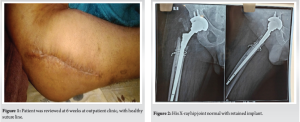

- He completed a total of 6-week course of Ceftriaxone 2 g 12 hourly (2 weeks as an inpatient and 4 weeks as an outpatient). The patient was reviewed at 6 weeks at outpatient clinic, with healthy suture line (Fig. 1) and all inflammatory markers were normal. His X-ray hip joint (Fig. 2) normal with retained implant. The clinical examination of hip was normal. There was no evidence of clinical, radiological, or microbiological treatment failure at follow-up. He came for follow-up at orthopedic outpatient department and the X-ray (Fig. 3) shows the X-ray hip joint with no evidence of bony involvement, no lysis or periosteal reaction suggestive of osteomyelitis and hip joint can bear weight normally (Fig. 4). He will be followed up at 8 months and 12 months to ensure no relapse.